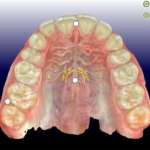

In questo articolo viene presentato un protocollo nuovo e diverso di gestione del bite nei pazienti affetti da dolori neuromuscolari e disordini temporo mandibolari mediante un bite che coinvolge il paziente a effettuare esercizi orali attivi fisici, cognitivi e rieducativi per stimolare la riorganizzazione dinamico funzionale e probabilmente nel tempo anche la neuroplasticità cerebrale.

Disfunzioni gnatologiche, ortodontiche e cranio-cervico-mandibolari: evoluzione dell’approccio strumentale Premium

Viene proposta una metodica per diagnosticare alterazioni patologiche dell’ATM, dei mascellari, delle vertebre cervicali, mettere in relazione queste strutture anatomiche e applicare alle loro immagini i riferimenti di tracciati cefalometrici già conosciuti e/o nuove correlazioni.